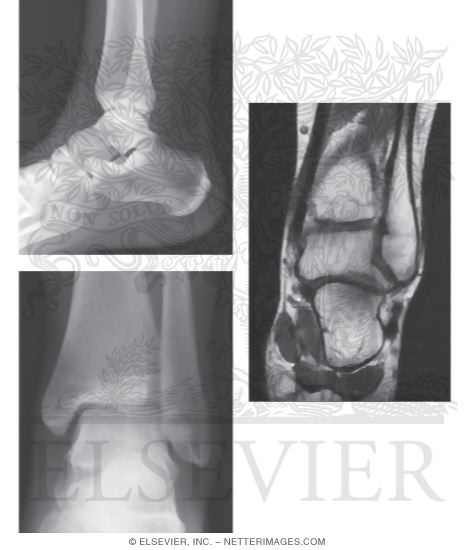

Ankle arthrodesis dissertation image This picture representes ankle arthrodesis dissertation.